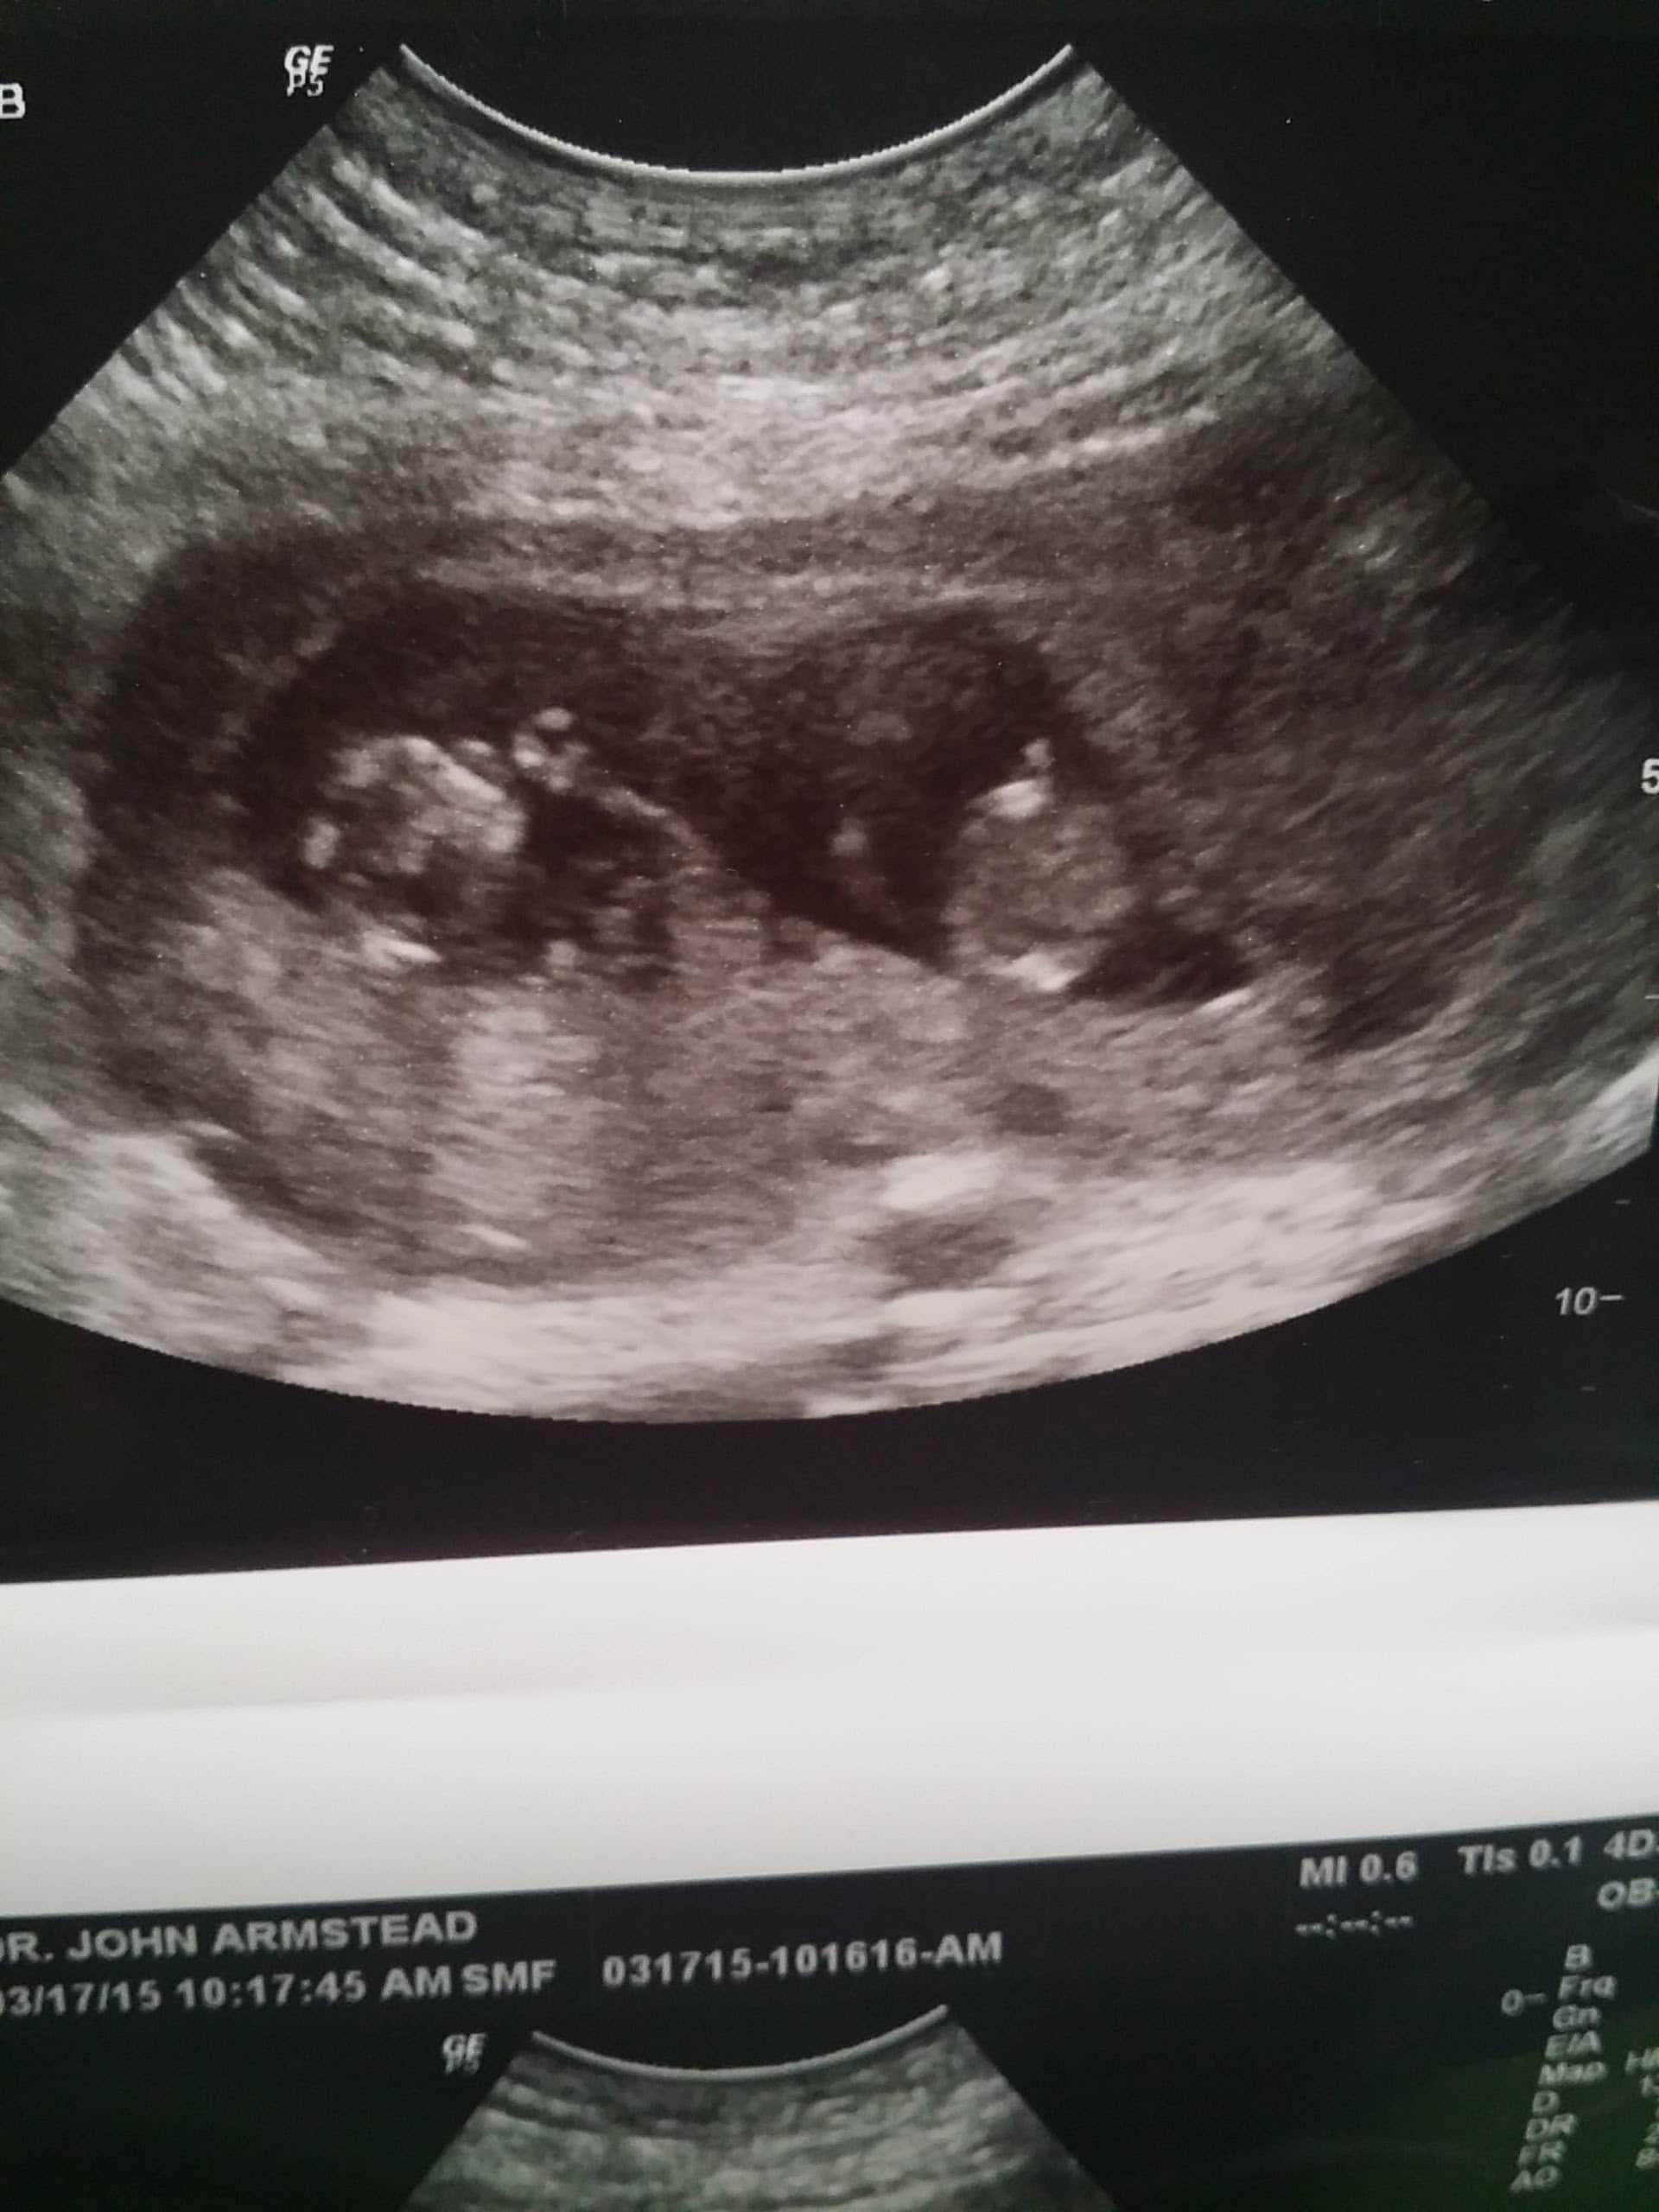

- Ultrasound Photos at 11 Weeks Pregnant With Twins

Ultrasound Photos at 11 Weeks Pregnant With Twins